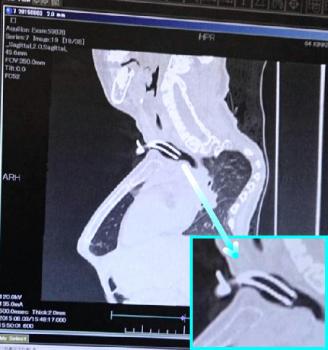

21時を過ぎた頃、CTび画像を見ながら先生からの説明があった。

以前のカニューレの画像(約5年前)

入れ替えて貰ったカニューレは、なんとか良い位置で収まっているらしい。

創太は気道の変形もあるので、より合う形のカニューレを探して下さるとの事だった。

今回のカニューレの画像

肺や脳の画像も以前のものと比較しても殆ど変わらずの状態だった。